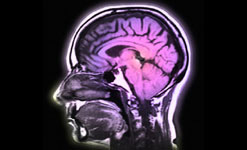

|  |  | | Blood Brain barrier on Material World | Blood Brain Barrier

The Blood Brain Barrier is an extraordinary mechanism.

Its been known about for well over 100 years but it’s only in the last 10 or 15 years that researchers have started to get an idea of the Blood Brain Barrier's role in diseases like MS, Alzheimer’s or Parkinson’s.

Quentin Cooper is joined by Professor Joan Abbott, Blood Brain Barrier group, King’s College, University of London and Professor Sanjay Sisodiya, Institute of Neuroscience, University College, University of London to find out more.